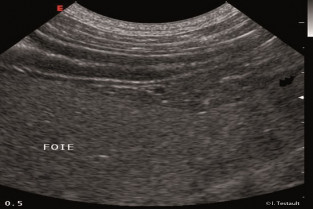

L’objectif du module central est d’instaurer un protocole standardisé pour l’examen échographique de l’abdomen. Les bases théoriques et pratiques de l’échographie, la topographie abdominale et l’aspect échographique normal des organes abdominaux seront également repris.

Les modules satellites se focalisent sur un appareil en particulier et permettent d’aborder l’aspect normal et lésionnel de chaque organe. L’intérêt et les indications de l’échographie interventionnelle sont également développés dans le module C.

- réaliser un examen échographique de l’abdomen

- identifier les différents organes abdominaux et réaliser sur chacun les coupes standard

- reconnaître les différentes structures anatomiques normales.